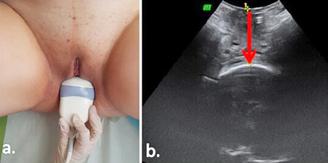

Examenul clinic local pune în evidență prezența unui vagin scurt, de 4 cm (prezintă doar vaginul inferior cu pliuri parțial păstrate), prolabat la nivelul vulvei, care se termină în fund de sac.

Imagine 1. Prolaps de boltă vaginală